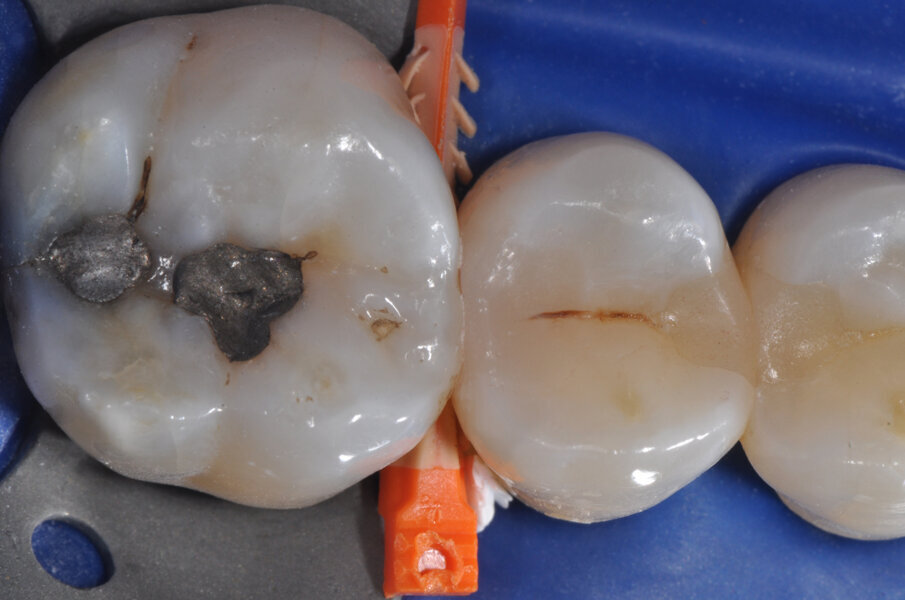

Il caso riguarda l’esecuzione di un restauro interprossimale col sistema di matrici sezionali anelli separatori e cunei Composi-Tight 3D Fusion. Il paziente presenta carie penetrante (D3) a carico dell’elemento 1.5 distale. Viene posizionata la diga di gomma (Fig. 1).

Viene posizionato un cuneo con matrice allo scopo di proteggere il dente aprossimale (Fig. 2). La cavità è stata preparata, la carie asportata, i margini cavitari devono essere rifiniti (Fig. 3). Vengono rimossi il cuneo e la matrice per meglio rifinire il gradino cervicale e per valutare che tipo di cuneo utilizzare (Fig. 4). Ai fini di migliorare l’adattamento della matrice viene utilizzata una striscia abrasiva in plastica di grana media (Fig. 5).